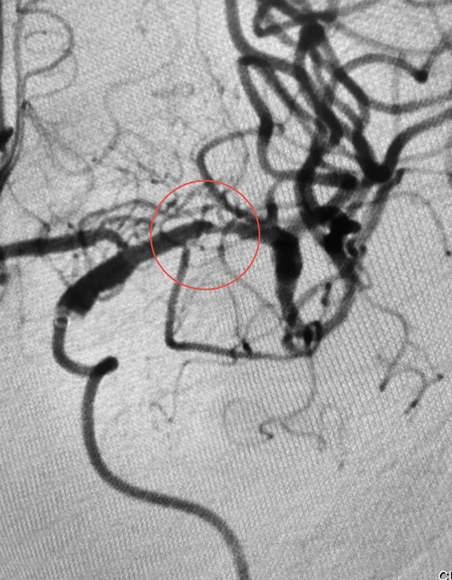

在紧张而有序的准备工作完成后,姜先生的手术于14时40分左右正式开始。手术过程中,医生们成功运用同轴技术超选至闭塞处,并确认真腔后,迅速从中间导管中抽吸出一块红色质地稍硬的血栓。随着血栓的顺利取出,造影结果显示远端血流复流良好。为了确保手术效果的稳定,医生们继续对姜先生进行了30分钟的密切观察。在这期间,造影结果始终显示血管畅通无阻,未再出现闭塞的情况。这标志着此次手术的成功。

▲血管闭塞△ ▲取栓成功后△